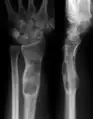

| X-ray image showing enchondromas localized in the lower part of the radius of a 7-year-old girl with Ollier disease. | |

Abnormal bone growth such as shortening or thickening and deformity may be observed in patients of Ollier disease. These bone lesions are visible at birth using radiography but are usually not screened or examined for until clinical manifestations present during early childhood. However, some patients may exhibit no signs of any symptoms.[1] One study found thirteen to be the mean age of diagnosis in patients with Ollier disease. In an X-ray, there would normally be the presence of several homogeneous lesions of an oval or elongated shape with bone edges that are slightly thickened.[3] With age, these lesions may calcify and appear as diffusely minute spots or stippled. Fan-like septations or streaks would be indicative of the presence of several enchondromas. Early detection and consistent and repeated monitoring is important in order to prevent and treat any potential bone neoplasms.

X-ray showing enchondromas localized in the lower part of the radius of a 37-year-old patient affected with Ollier disease